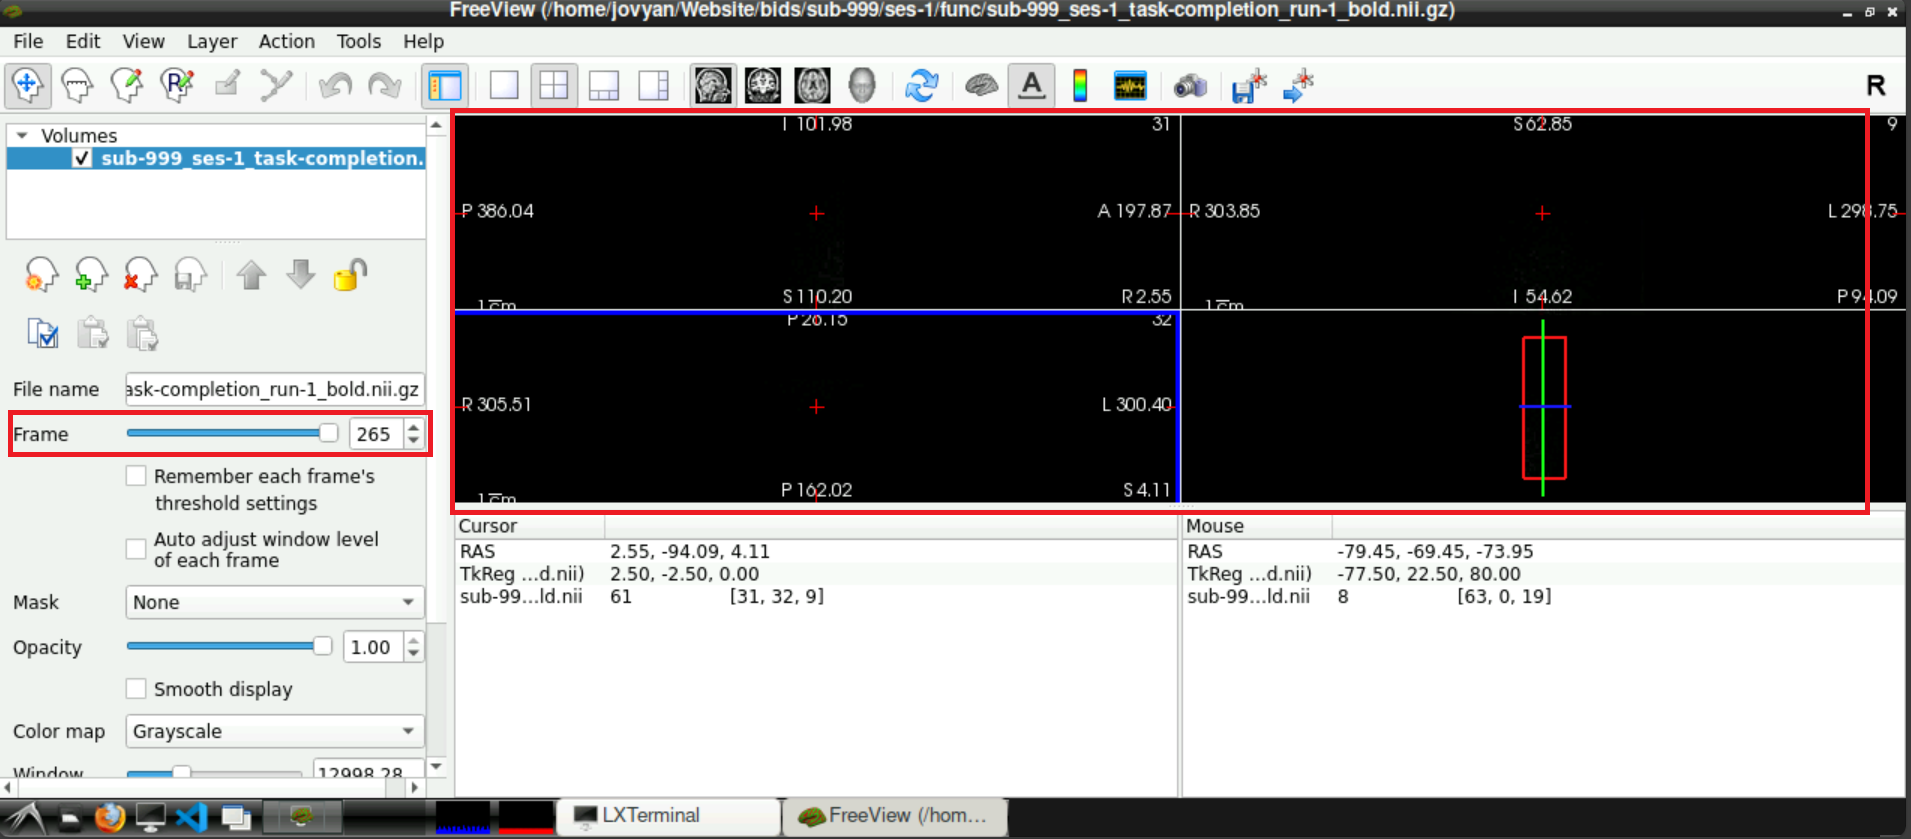

1.3 Check for Denoising Scan

To check if a denoising scan is included in you data, use the slider next to Frames (left side, roughly in the middle), to navigate to the last frame. If a denoising sequence was used during data acquisition in the scanner, this frame looks “empty”. Toggle between the last and second to last frame, to visualize the difference even more